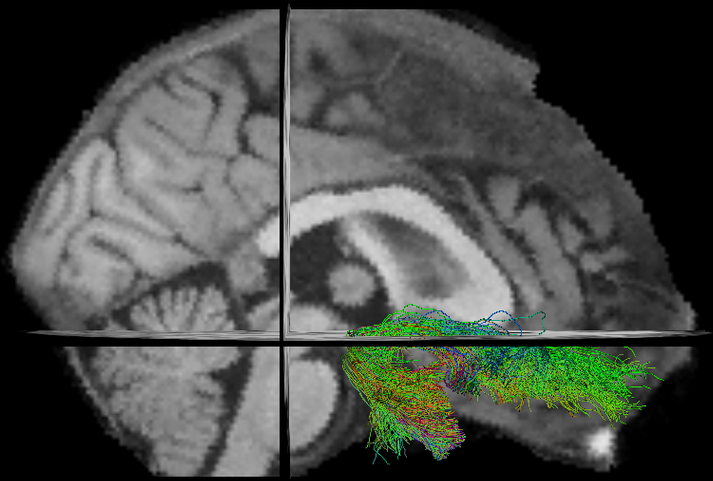

- TractFiltering (Cousineau et al 2016. ISMRM, Coté et al 2015. ISMRM)

- Tractometry (Cousineau et al 2016. ISMRM)

FA

NUFO

Metrics

- Mean value per bundle

- Mean value per point

- Profile

- Volume

Project: Catherine Vien, Julien Doyon